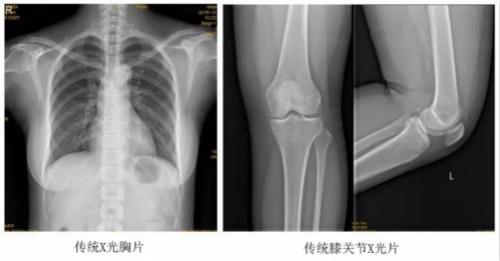

临床在诊治脊柱及下肢畸形时,往往采取矫正手术治疗。这就需要在对其进行手术前后,拍摄全脊柱或全下肢的X光片作为诊治依据,以便分析病情、制定手术方案和评估术后疗效。目前大部分医院使用的DR摄片机,因拍摄幅面受限,最大规格43cm,但成人的全脊柱长度一般约60cm,而全下肢更长,不能一次性拍摄出完整的全脊柱或全下肢的X光影像。以全脊柱摄片为例,各拍摄一张传统的颈椎、胸椎、腰椎的X片虽然就能观察到每个部位局部的侧弯情况,但不能观察到三者之间的连续性。因此传统X光片在这类疾病诊断上存在着一定的缺陷,无法更精准有效地进行临床诊断和治疗。

以某院所摄X光片为例,对比传统摄片与全身拼接功能的区别:

传统X光片只能观察每个部位的局部情况,无法在统一体上进行连续、全面的观察,全脊柱及下肢全长片则能直观的看到整体形变。通过DR全身拼接功能实现的完整成像,为诊治脊柱及下肢畸形提供了完美的临床影像依据,对临床诊断、术前手术方案的制定和术后疗效的评估等临床应用具有十分重要的意义,有效满足了此类疾病临床诊断和治疗的要求。